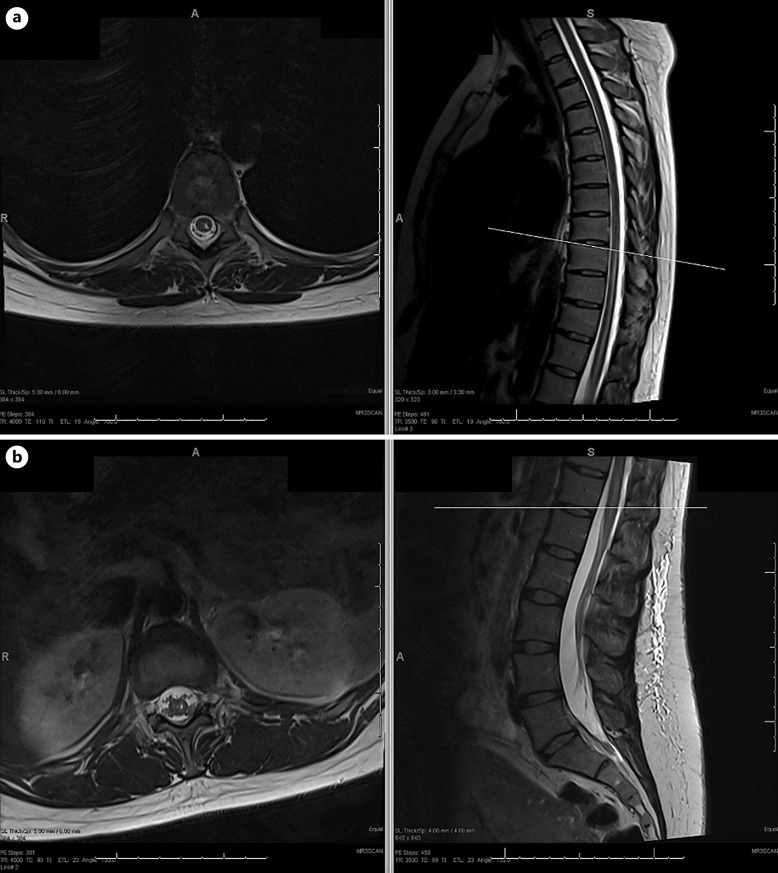

Case presentation: We present a 38-year-old female patient who presented with left lower extremity weakness, loss of temperature sensation, and urinary retention following spinal anesthesia for cesarian section. Magnetic resonance imaging of the spine demonstrated T2 hyperintensities in the left central spinal cord from T8 to the conus medullaris. A diagnosis of spinal cord infarction was made after lumbar puncture testing showed no evidence of inflammatory myelitis. The patient was treated with steroids empirically until lumbar puncture testing showed no inflammation. The patient was discharged on daily aspirin with persistent left lower extremity weakness and loss of temperature sensation. A plan for outpatient physical therapy was made for rehabilitation.